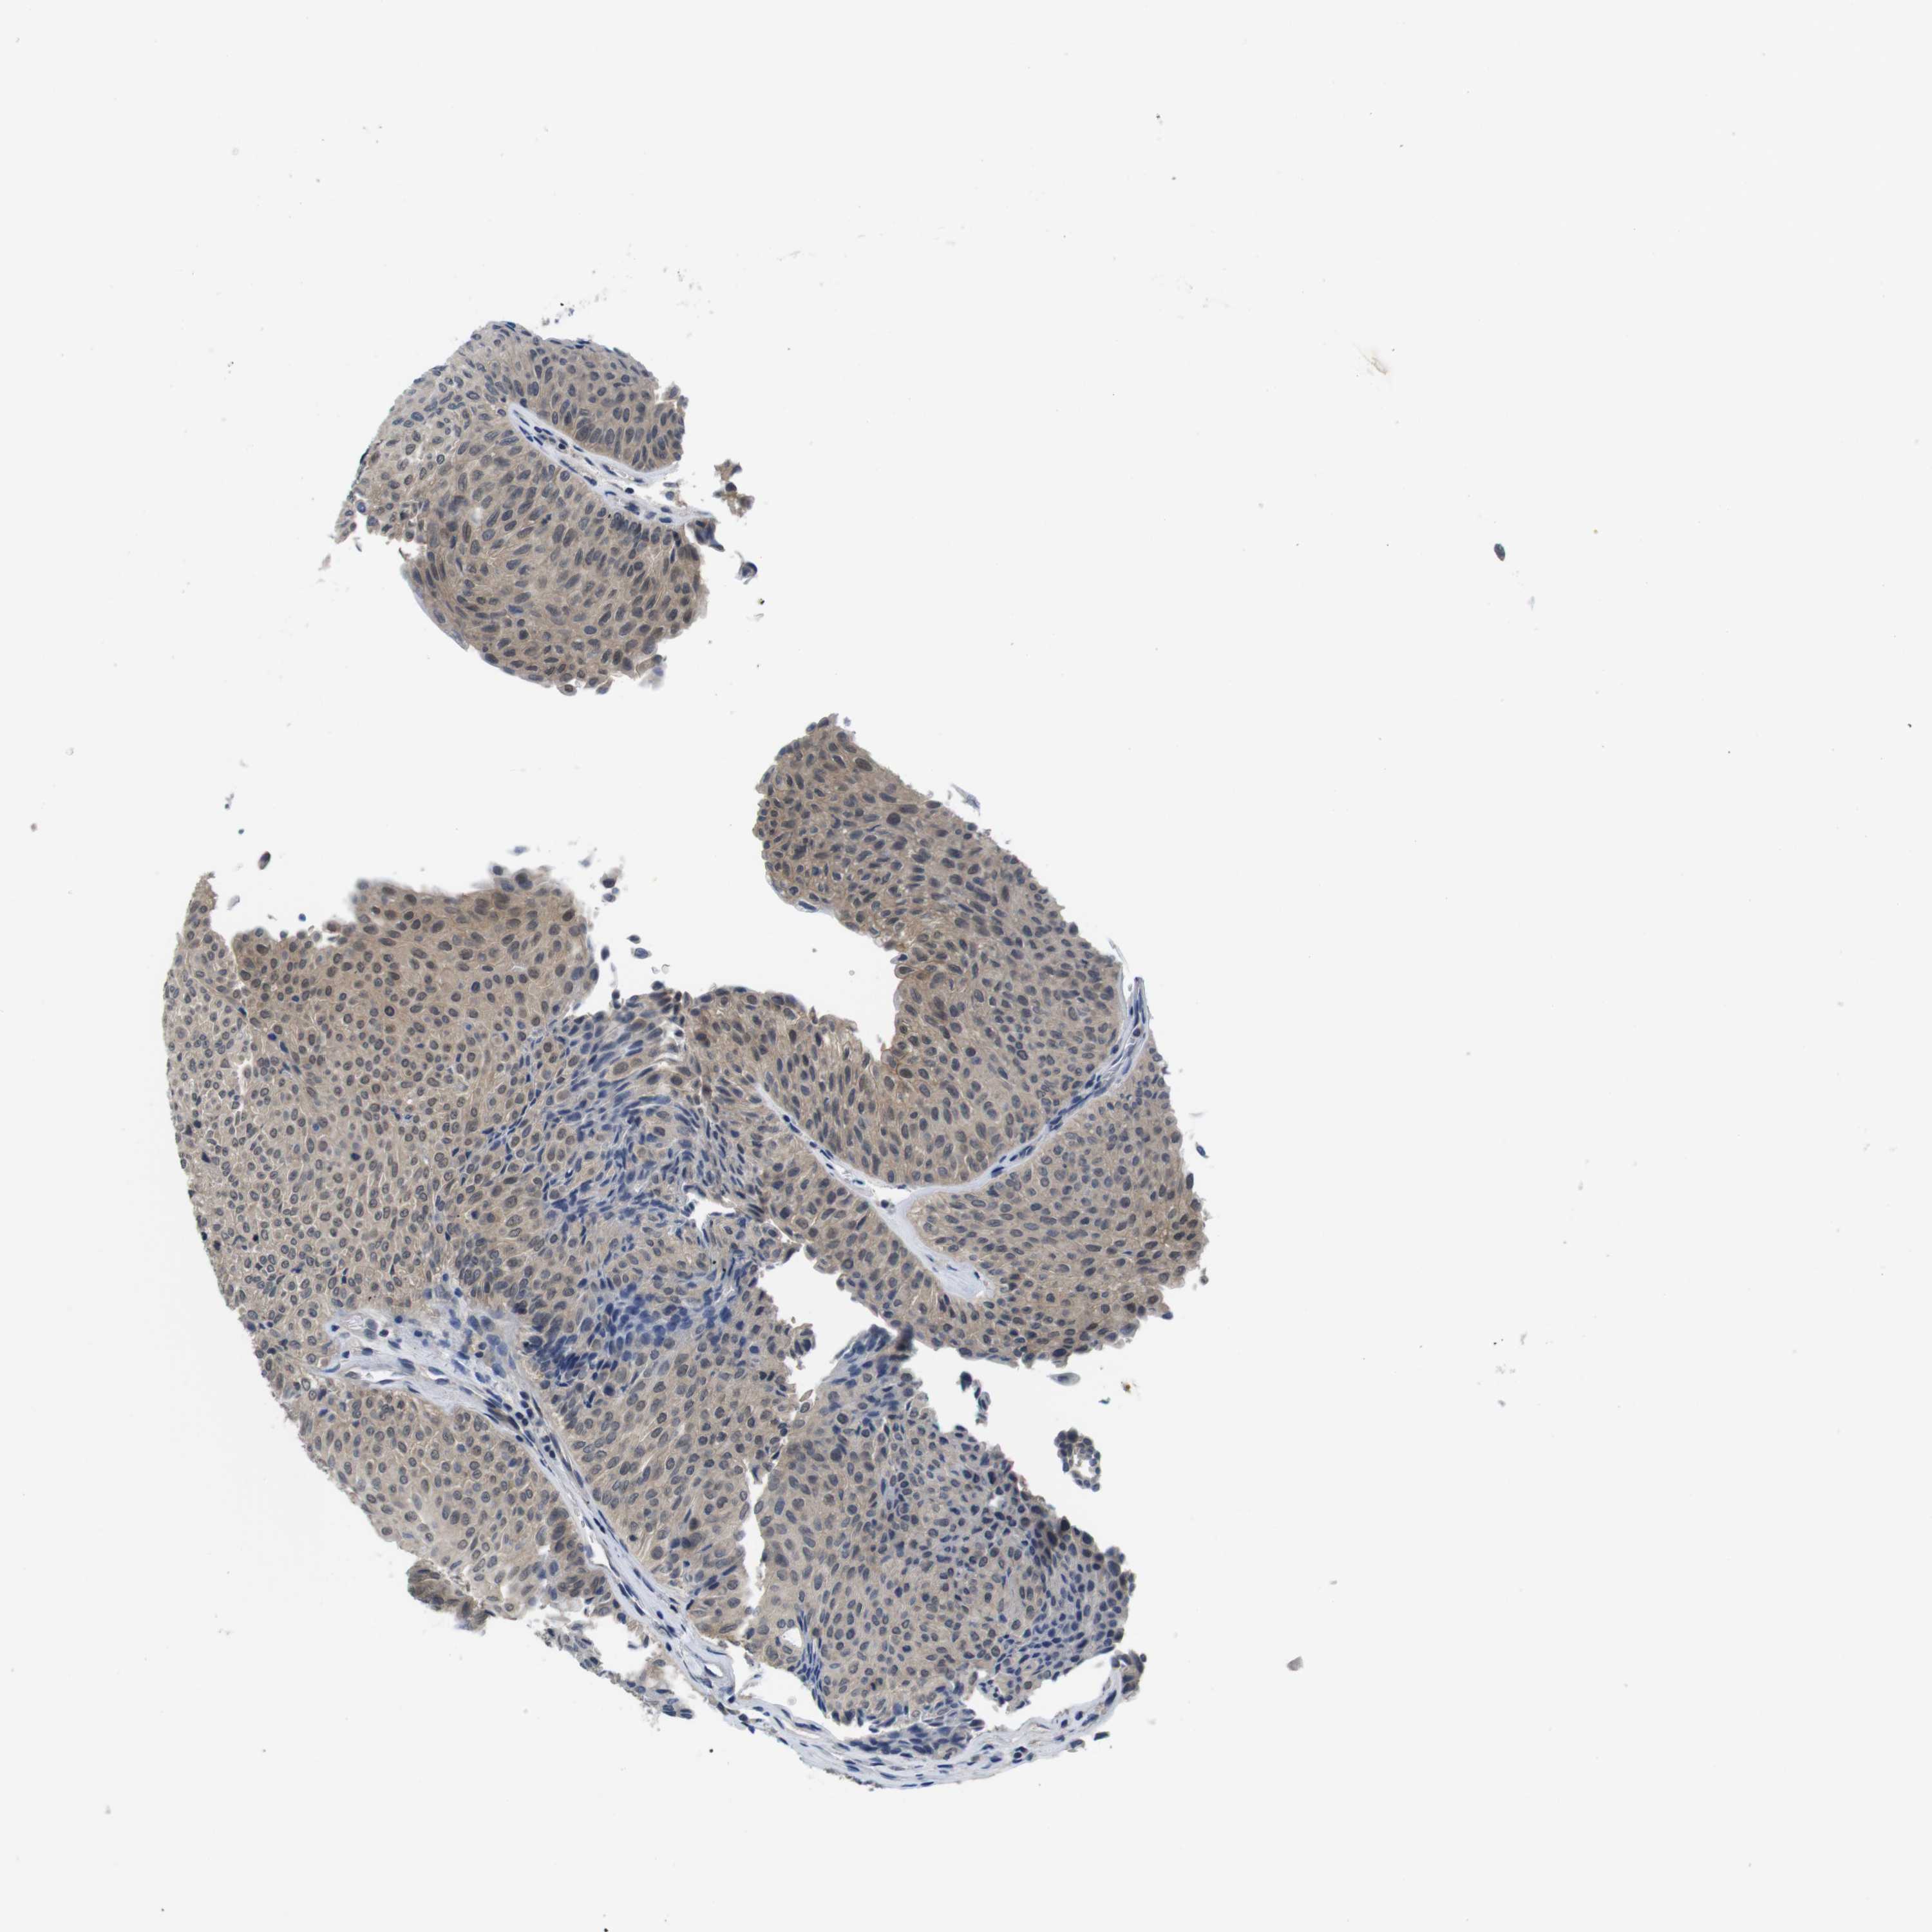

UROTHELIAL CANCER - Protein expressioni

A mouse-over function shows sample information and annotation data. Click on an image to view it in a full screen mode. Samples can be filtered based on level of antibody staining by selecting one or several of the following categories: high, medium, low and not detected. The assay and annotation is described here.

Note that samples used for immunohistochemistry by the Human Protein Atlas do not correspond to samples in the TCGA dataset.

Antibody stainingi

Antibody staining in the annotated cell types in the current human tissue is reported as not detected, low, medium, or high, based on conventional immunohistochemistry profiling in selected tissues. This score is based on the combination of the staining intensity and fraction of stained cells.

Each image is clickable and will lead to virtual microscopy that enables deeper exploration of all samples and also displays staining intensity scores, fraction scores and subcellular localization as well as patient and tissue information for each sample.

Antibody HPA001464

Antibody CAB010209

Urothelial carcinoma, Low grade

Urothelial carcinoma, High grade